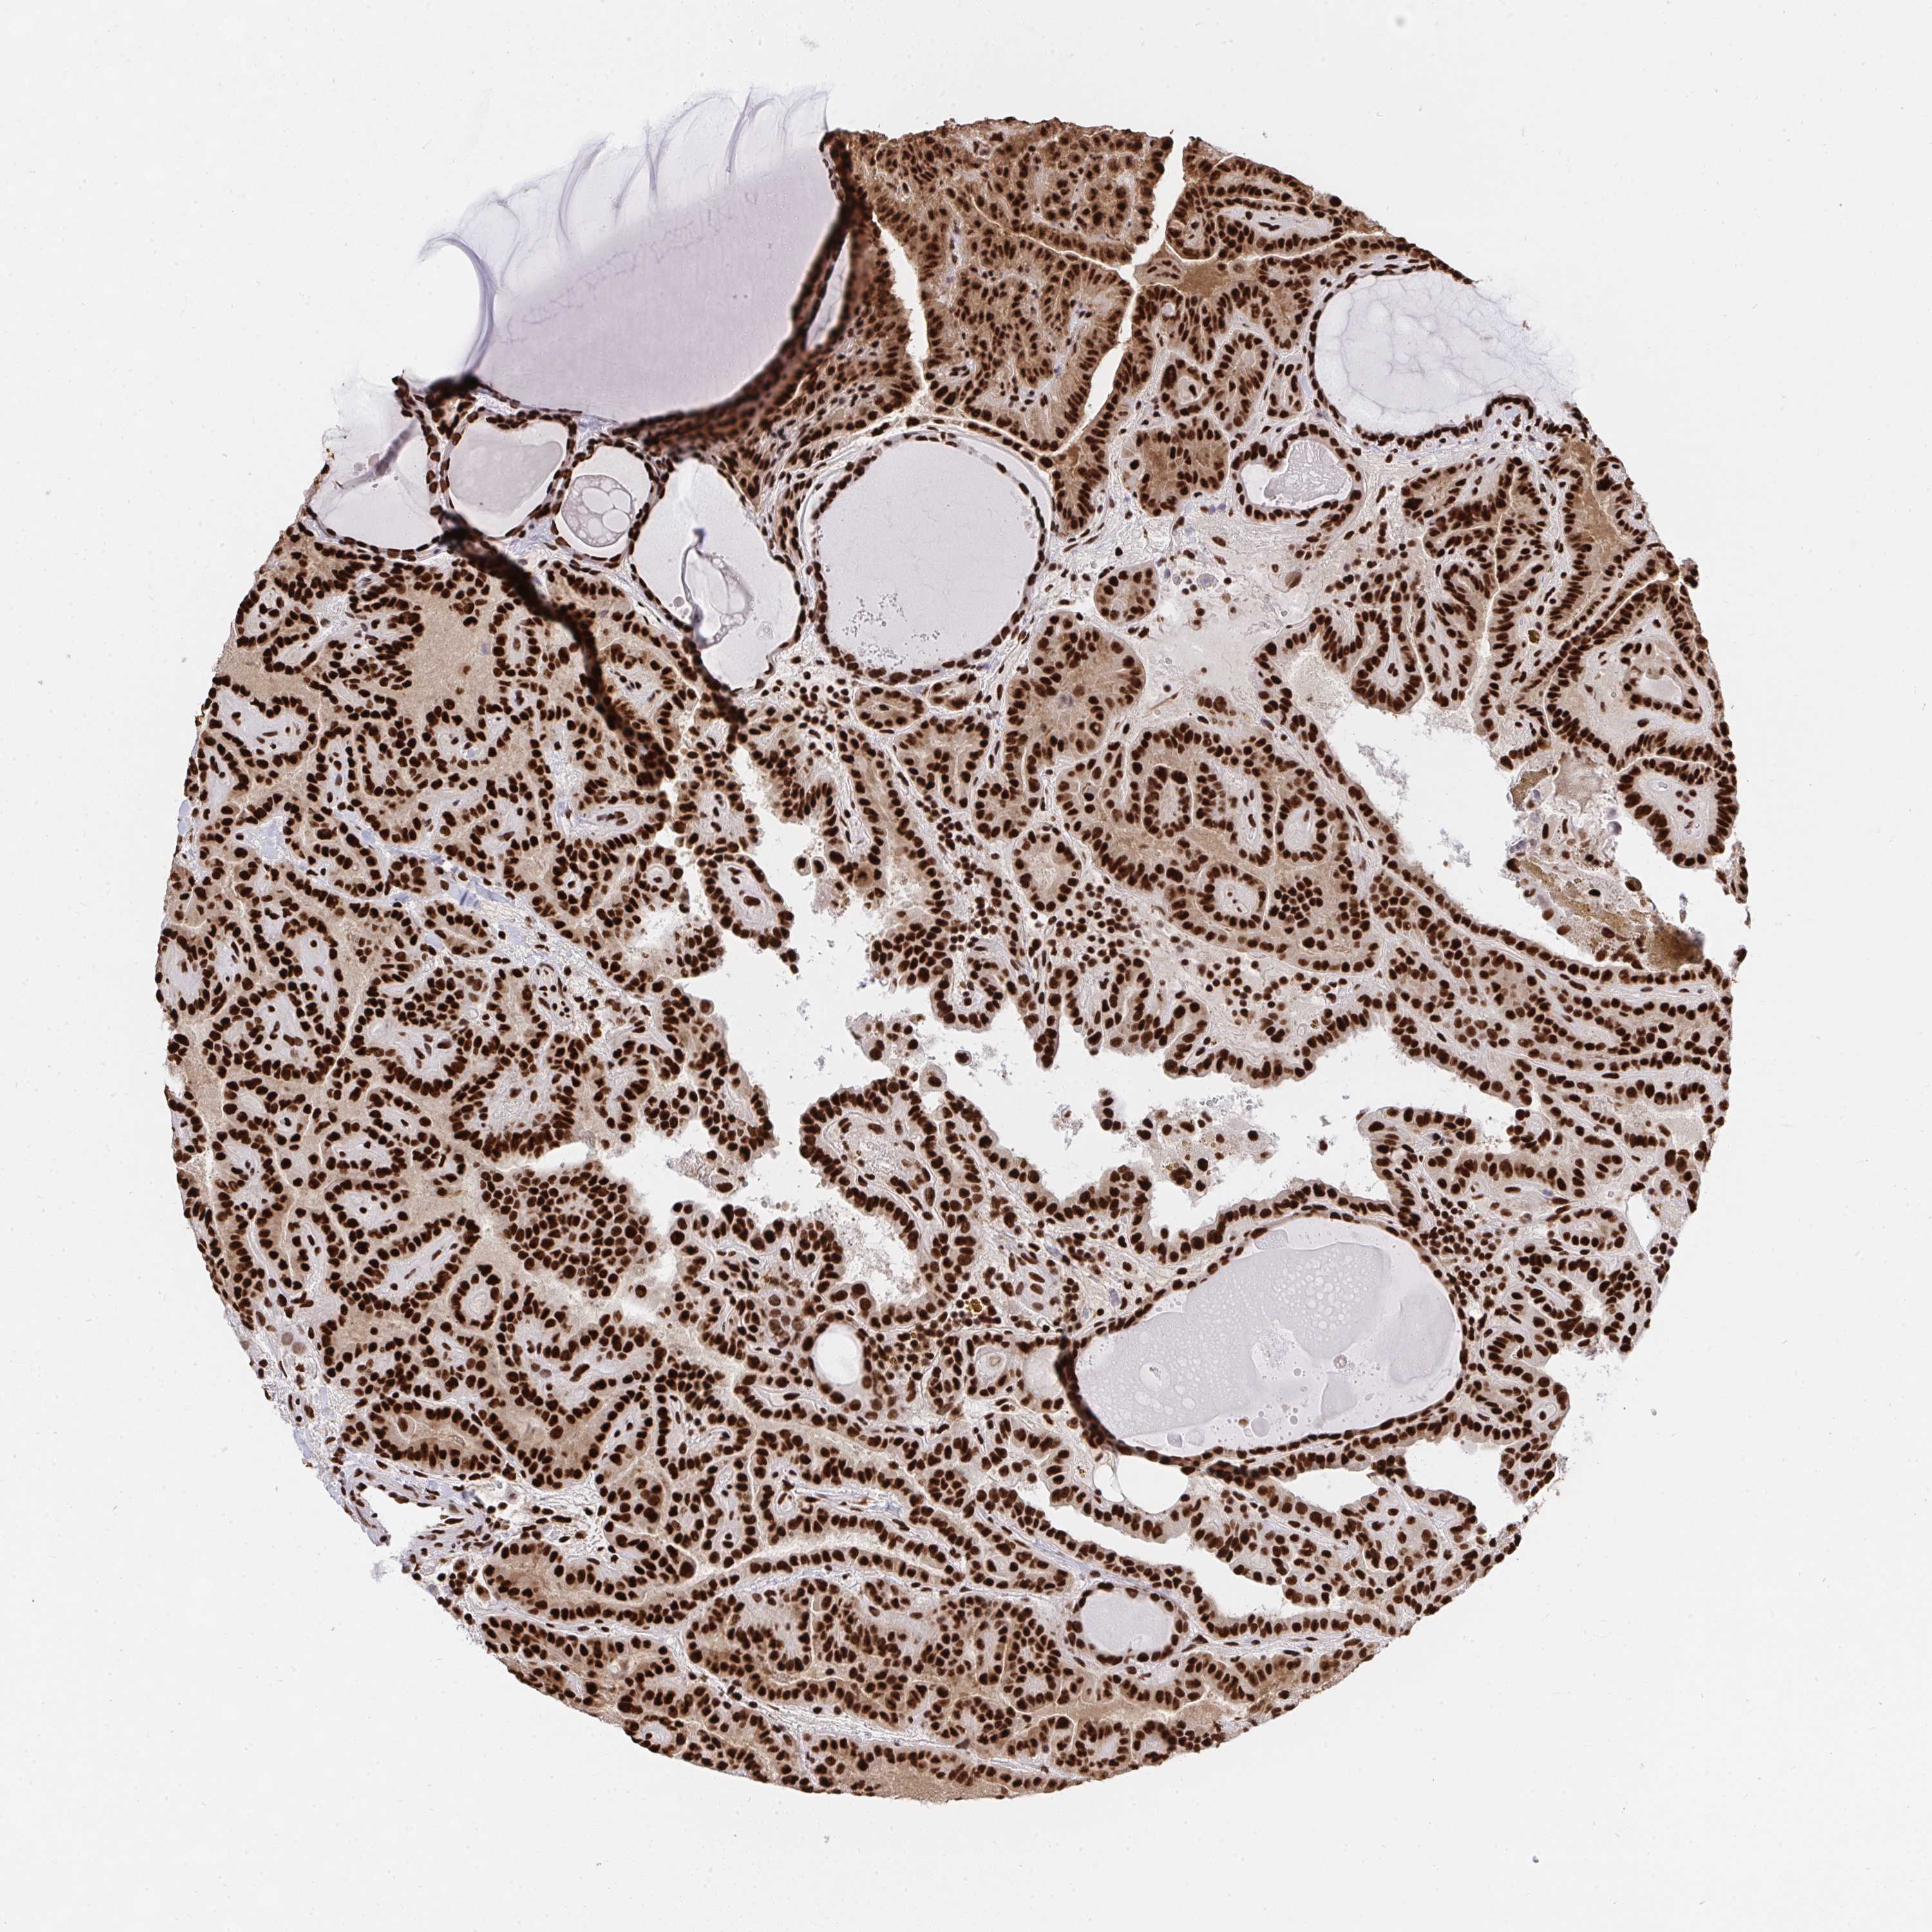

THYROID CANCER - Protein expressioni

A mouse-over function shows sample information and annotation data. Click on an image to view it in a full screen mode. Samples can be filtered based on level of antibody staining by selecting one or several of the following categories: high, medium, low and not detected. The assay and annotation is described here.

Note that samples used for immunohistochemistry by the Human Protein Atlas do not correspond to samples in the TCGA dataset.

Antibody stainingi

Antibody staining in the annotated cell types in the current human tissue is reported as not detected, low, medium, or high, based on conventional immunohistochemistry profiling in selected tissues. This score is based on the combination of the staining intensity and fraction of stained cells.

Each image is clickable and will lead to virtual microscopy that enables deeper exploration of all samples and also displays staining intensity scores, fraction scores and subcellular localization as well as patient and tissue information for each sample.

Antibody HPA051748

Antibody HPA052661

Antibody CAB016326

Staining

High

Medium

Low

Not detected

Intensity

Strong

Moderate

Weak

Negative

Quantity

>75%

75%-25%

<25%

None

Location

Nuclear

Cytoplasmic/membranous

Cytoplasmic/membranous,nuclear

Papillary adenocarcinoma, NOS

Follicular adenoma carcinoma, NOS